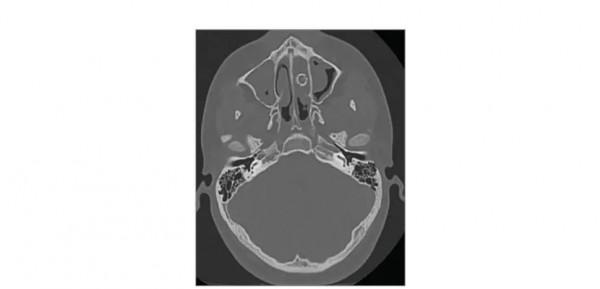

CT掃描顯示男孩鼻子裡有一個9毫米的金屬BB彈,大約8年的時間裡,男孩從未意識到這一點。(圖片來源:JAMA Network,2021 American Medical Association)

一名男孩數年以來一直遭受鼻塞和嗅覺下降的困擾, 15歲時他終於決定去問診。研究者發現當患者擤鼻涕時,房間裡會出現“刺鼻的惡臭”。CT掃描顯示,患者鼻腔中有一個直徑9毫米的球形結構。手術移除該物體後,發現這是一個金屬BB彈。